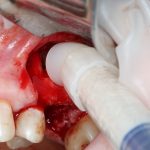

Кстати, обрати внимание на ширину альвеолярного гребня (левая картинка). Она чуть меньше 3 мм. Это объясняет, почему я засомневался в возможности установки имплантатов одновременно с остеопластикой. Понятно и без КЛКТ.

Наперво, мне нужно удалить разрушенный зуб и получить костный аутотрансплантат.

Для получения костного блока, мы открываем донорскую зону, наружную косую линию нижней челюсти.